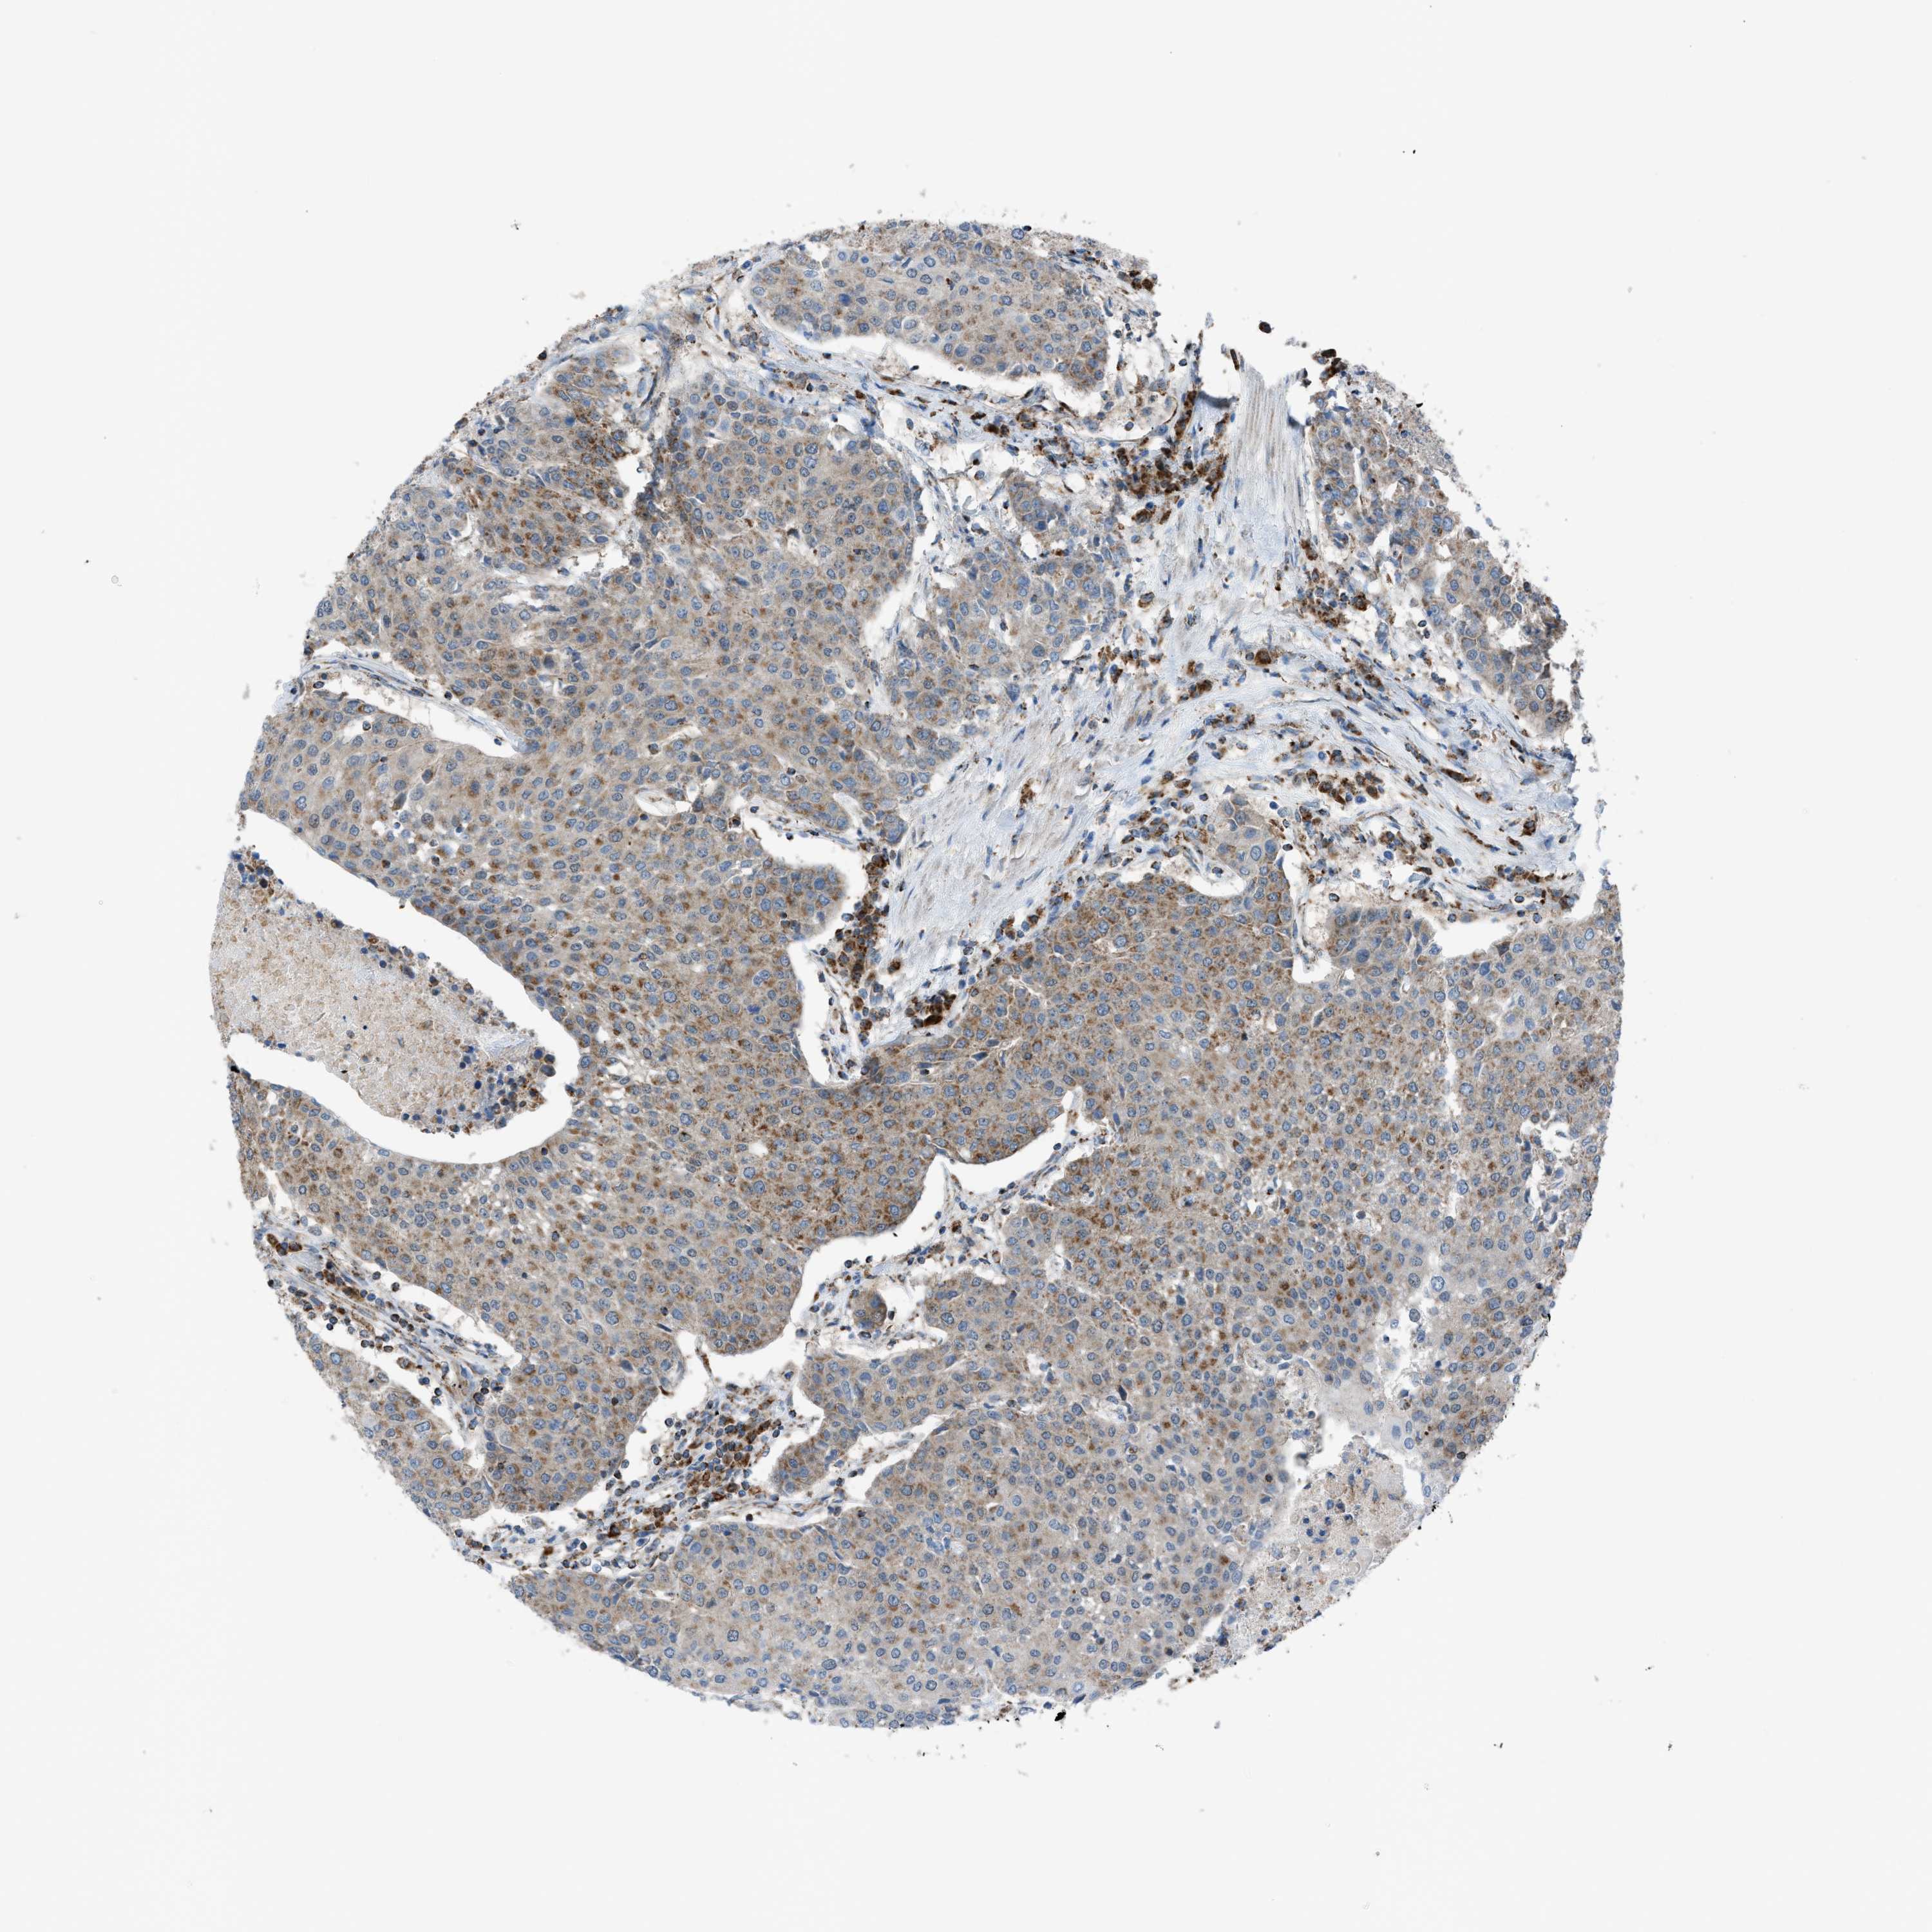

UROTHELIAL CANCER - Protein expressioni

A mouse-over function shows sample information and annotation data. Click on an image to view it in a full screen mode. Samples can be filtered based on level of antibody staining by selecting one or several of the following categories: high, medium, low and not detected. The assay and annotation is described here.

Note that samples used for immunohistochemistry by the Human Protein Atlas do not correspond to samples in the TCGA dataset.

Antibody stainingi

Antibody staining in the annotated cell types in the current human tissue is reported as not detected, low, medium, or high, based on conventional immunohistochemistry profiling in selected tissues. This score is based on the combination of the staining intensity and fraction of stained cells.

Each image is clickable and will lead to virtual microscopy that enables deeper exploration of all samples and also displays staining intensity scores, fraction scores and subcellular localization as well as patient and tissue information for each sample.

Antibody HPA015746

Staining

High

Medium

Low

Not detected

Intensity

Strong

Moderate

Weak

Negative

Quantity

>75%

75%-25%

<25%

None

Location

Nuclear

Cytoplasmic/membranous

Cytoplasmic/membranous,nuclear

Urothelial carcinoma, Low grade

Urothelial carcinoma, High grade